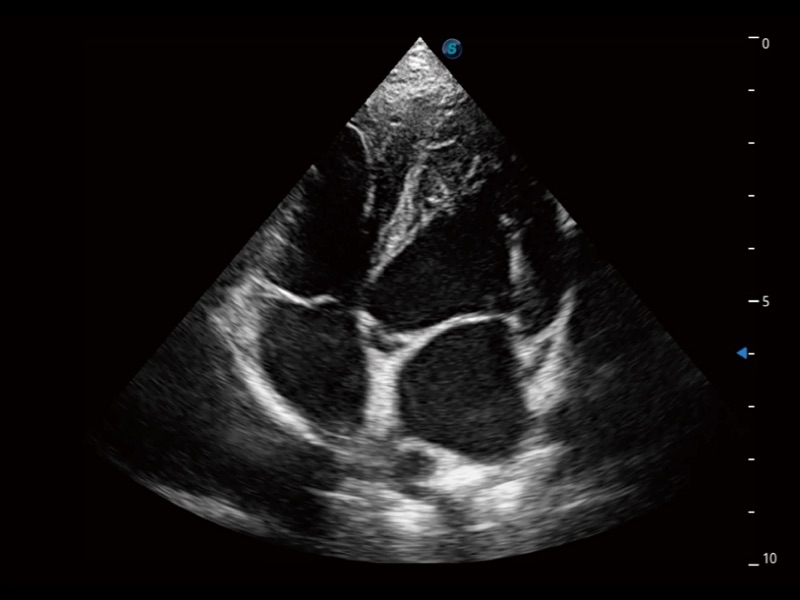

通過(guò)360度任意調(diào)節(jié)3條M型取樣線,在同一心動(dòng)周期上觀察心臟不同位置的運(yùn)動(dòng)曲線,得到準(zhǔn)確的心功能測(cè)量數(shù)據(jù),有效評(píng)估心肌運(yùn)動(dòng)及左心室功能。

實(shí)時(shí)用顏色表示心肌組織運(yùn)動(dòng),觀察和定量組織的運(yùn)動(dòng)情況,對(duì)快速檢測(cè)與評(píng)估心肌的灌注和活性、電傳導(dǎo)及心肌收縮和舒張功能等均能提供重要的診斷信息。